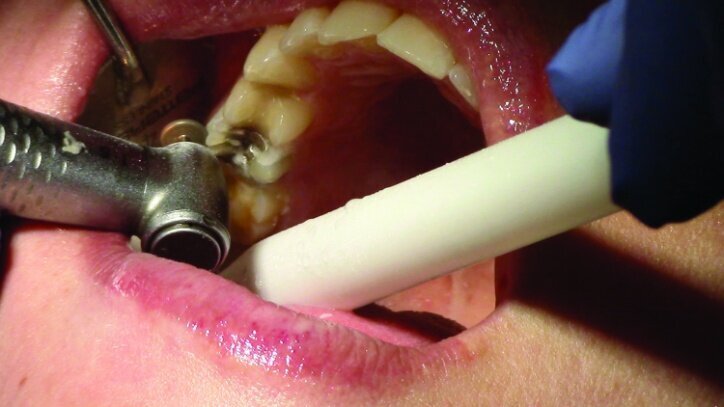

Depth guide cuts were made using a 330 bur, which has a 2 mm cutting surface (Figs. 2a–3b). This ensures 2 mm of occlusal reduction to accommodate 2 mm of material thickness on the occlusal surface of the restoration.

Gross occlusal reduction was completed using a KS7 bur to the depth cuts (Figs. 4–8b, 9c). Adequate clearance was verified with a 2 mm prep check from Common Sense Dental Products.